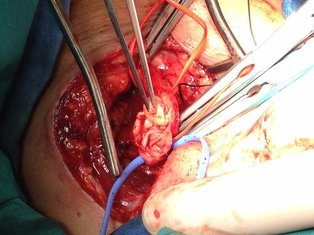

Boyuna karotis damar üzerindeki cildin 5cm'lik kısmına lokal anestezi uygulanır. Daha sonra 4-5cm'lil kesiden damara ulaşılır. Damar duvarı açılır ve damar içerisindeki plak çıkartılarak damar direk veya yama konularak kapatılır. Ortalama operasyon süresi 1.5-2 saat civarındadır.

Resim 1,2. Karotis endarterektomi (Karotis damar içerisinden plak çıkarımı)